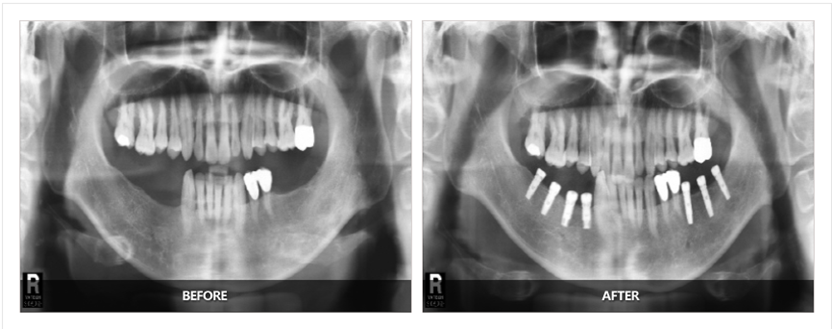

拓展知識(shí):種植牙基臺(tái)應(yīng)該漏出多少